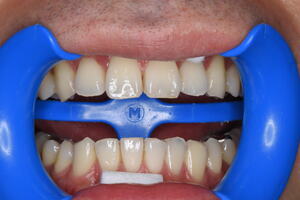

技工士がハンドメイドで作成したものには劣る(適合、形態)

装着が煩雑でフロスが引っ掛かるケースが多い(歯科医師のテクニカルエラー)